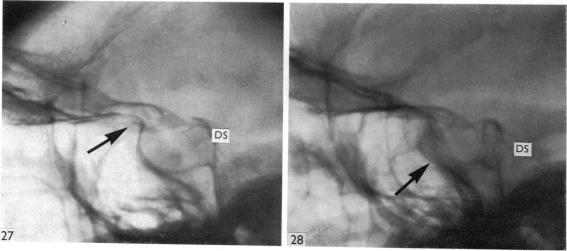

Surgical aspects of the anatomy of the sphenoidal sinuses and the sella turcica.

J Anat. 1977 Dec;124(Pt 3):541-53.